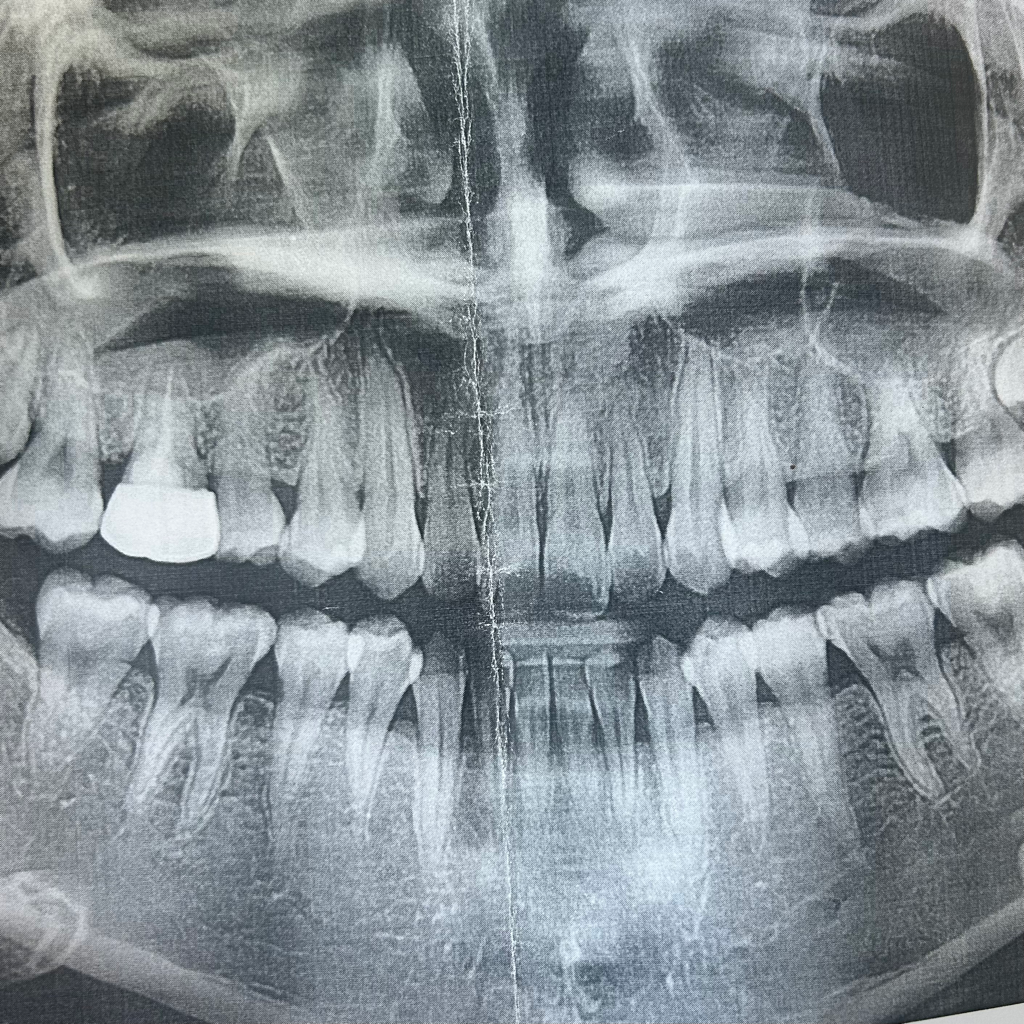

• 3번 째 사진

파노라마만으로는 인접면 충치를 판단하기는 어렵습니다. 아래 작은 사진을 보게되면 깊은 충치가 보이진 않습니다.